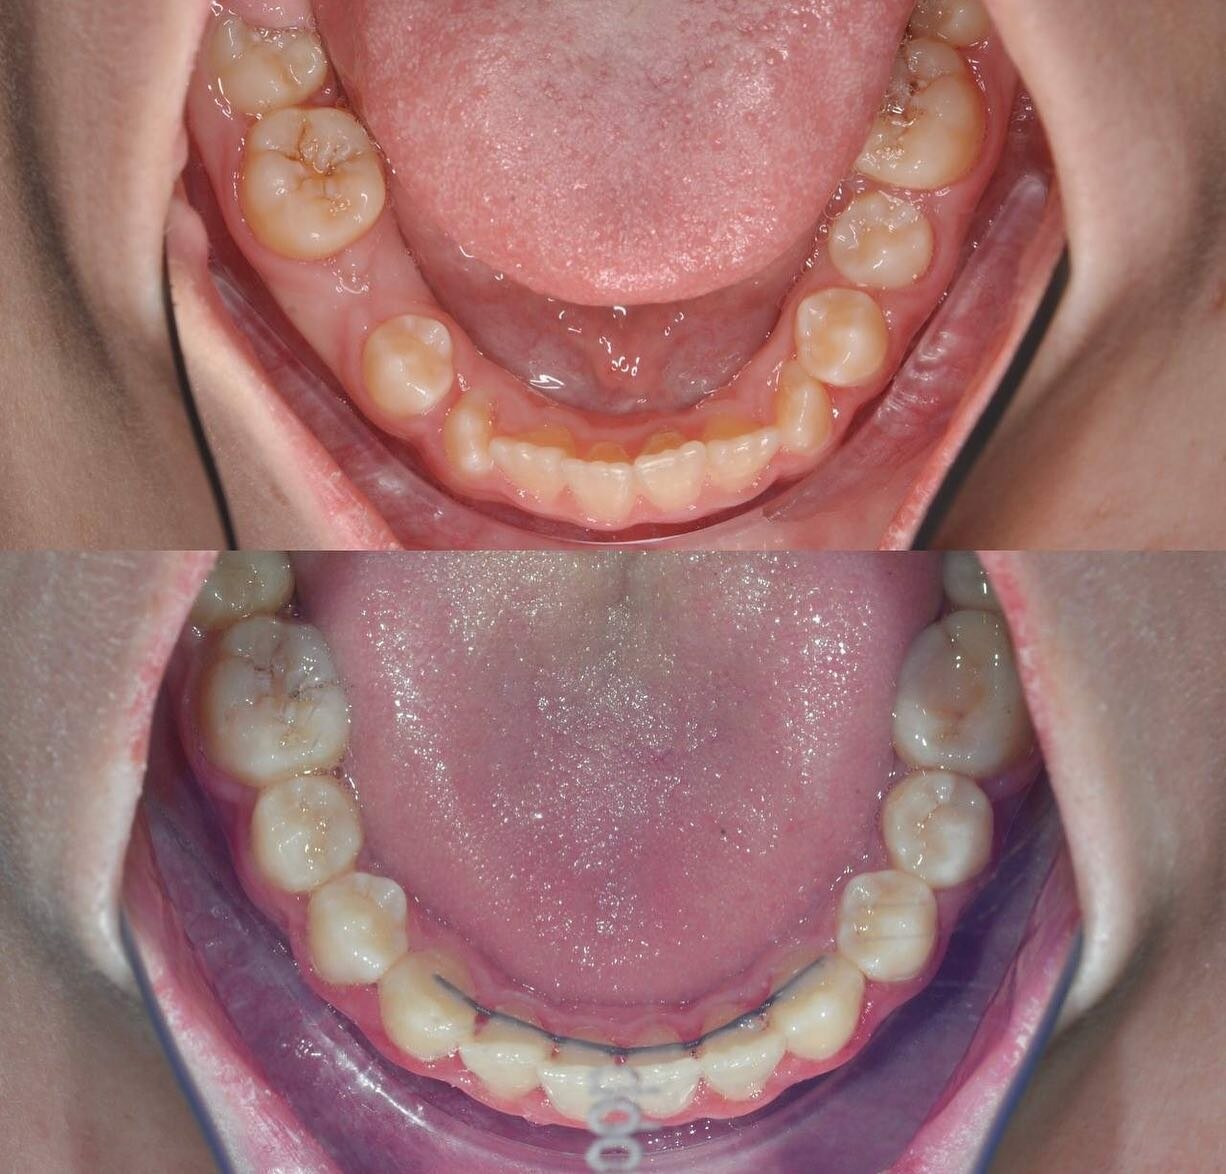

Клиника предоставляет услуги по всем основным направлениям стоматологии, включая общую стоматологию, ортодонтию, хирургическую и эстетическую стоматологию, а также детскую стоматологию. Среди дополнительных услуг: лечение кариеса, пломбирование, удаление зубов, имплантация, протезирование, отбеливание, установка виниров и брекетов, лечение десен и каналов, рентгенография, челюстно-лицевая хирургия и френулопластика.

- пломбирование

- лечение кариеса

- гигиена полости рта